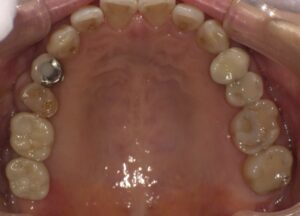

左はインプラントを入れる前に右は入れた後になります。向かって左側の歯が増えて

よく噛めるようになりました。